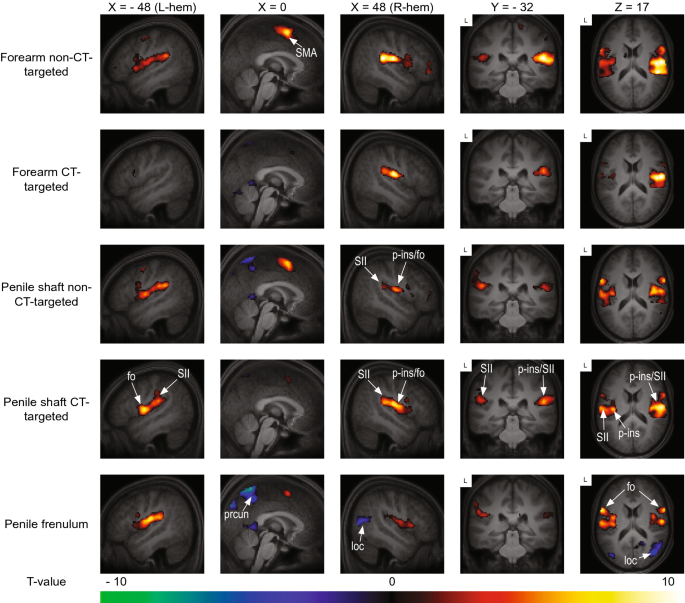

Both tactile stimulation of forearm and penis evoked significant activation of S2, pINS supplementary motor cortex (SMA), lateral precentral gyrus, and parts of the superior temporal gyrus (p < 0.05 family wise error [FWE] corrected). S2 is located in the upper bank of the lateral sulcus and includes the most lateral aspect of the postcentral gyrus and the central and parietal operculum37. As can be seen in Fig. 2 and Table 1 there is remarkable overlap in brain response between the various conditions.

Group level results of the whole-brain analysis of each dynamic touch condition versus baseline (fixation). Red indicates activation relative to baseline, blue indicates deactivation relative to baseline. The template was created by averaging the structural T1-scans of the 19 participants. Results are presented at a threshold of p < 0.05 FWE-corrected. Abbreviations: frontal operculum (fo), lateral occipital cortex (loc), posterior insula (p-ins), precuneus (prcun), supplementary motor area (SMA), secondary somatosensory cortex (SII). FMRI sections were created using FSLeyes (v. 1.3.3; https://fsl.fmrib.ox.ac.uk/fsl/fslwiki/FSLeyes). Final figure was created using Adobe InDesign 2022 for Mac (v. 17.2; https://www.adobe.com/products/indesign.html).

Still, close visual inspection yields important differences between forearm and penile conditions. For the forearm, activation clusters in S2 are present bilaterally but have a strong emphasis on the right S2, which is contralateral to the brushing stimulation. For the penile shaft and frenulum, the differences between left and right S2 activity were smaller and more variable. Penile shaft stimulation also evoked significant activity in the ipsi- (both slow and fast stroking) and contralateral (only slow stroking) aINS, which was not the case for frenulum and forearm stimulation.

For the penile stimulation conditions, there was bilateral deactivation of the precuneus, with the strongest effect for frenulum stimulation. A similar but smaller effect was also found for the forearm, but only for CT-targeted stimulation. Additionally, there was deactivation of cerebellum (shaft CT-targeted and forearm CT-targeted), temporal occipital fusiform cortex (shaft CT-targeted and frenulum), lateral occipital cortex (shaft non-CT-targeted and frenulum), lingual gyrus (shaft CT-targeted and frenulum) and posterior cingulate cortex (shaft both CT- and non-CT-targeted and frenulum).